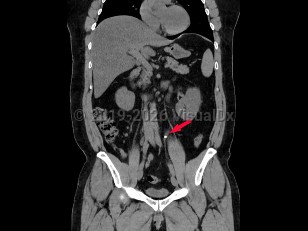

Abdominal aortic aneurysmAbdominal aortic aneurysm

Aortic dissectionAortic dissection

Ureteral calculus